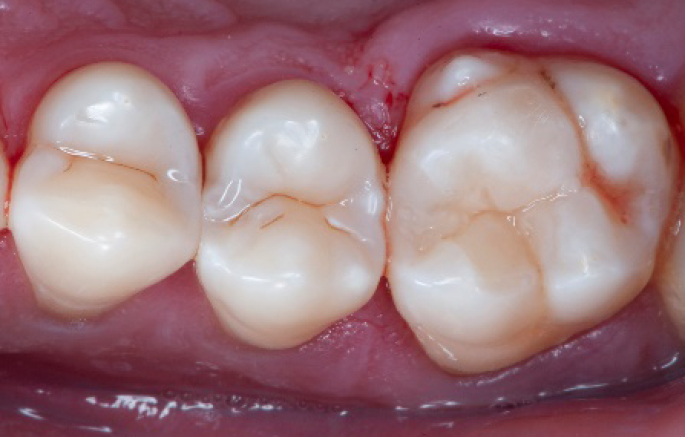

Step 12:

The situation after rubber dam removal.

Step 13:

Occlusal check

Step 14:

2 weeks control